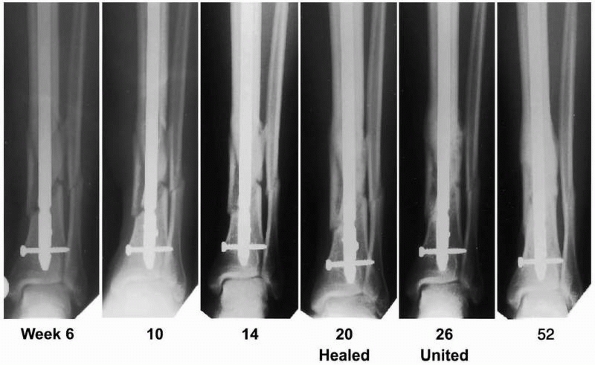

treatment of tibial nonunions (Fig. 5-3).

![]() |

|

FIGURE 5-3

Sequential radiographs of a tibial nonunion treated with recombinant human OP-1 immediately postoperatively and at 9 months and 24 months after intramedullary nailing. Note the bridging callus and subsequent tibial union. [Reprinted with permission from Friedlaender GE, Perry CR, Cole JD, et al. Osteogenic protein 1 (bone morphogenetic protein 7) in the treatment of tibial nonunions. J Bone Joint Surg Am 2001;83:S151-S158]. |